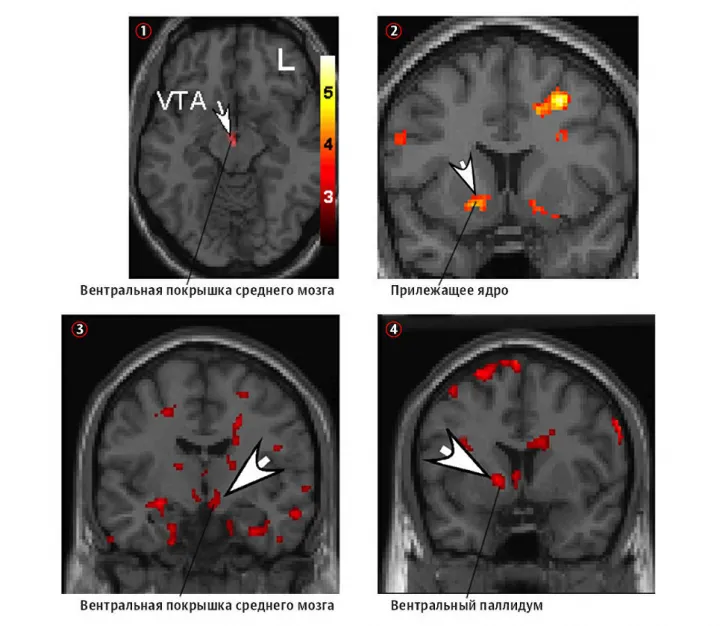

Сканы фМРТ, показывающие, как выглядит мозг любящих людей. Сканы фМРТ, показывающие, как выглядит мозг любящих людей.© historymed.ru

Хотя окситоцин чаще всего связан с романтической любовью, исследователи обнаружили, что именно активность BAS делает другого человека центром нашего внимания. Такой сногсшибательный эффект возникает из-за сочетания окситоцина с дофамином, — веществом, отвечающим за вознаграждение, которое в больших количествах выделяется во время романтической любви. По сути, влюблённость активирует в головном мозге пути, связанные с положительными чувствами.

Однако это ещё не всё, поскольку чувствительность BAS также влияет на высокую активность орбитофронтальной и префронтальной коры мозга. Когда мы достигаем желаемого — например, поцелуя, — вместе с этим запускаются также передняя поясная извилина и вентральное полосатое тело мозга. Всё это изменяет объём серого вещества в префронтальной коре и повышает уровни глутамата в сети вознаграждений.